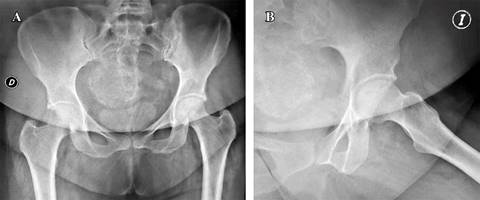

Figura 1: A) Radiografía anteroposterior de caderas con área de necrosis de cabeza femoral. B) Radiografía lateral de caderas con área de necrosis de cabeza femoral.

Figura 6: Control al momento de evaluación final de resultados radiográficos. Radiografía anteroposterior de caderas sin colapso de superficie articular.

Figura 7: Radiografía lateral de caderas sin colapso o progresión de enfermedad.

En los casos restantes, no se observó progresión adicional del daño de la cabeza femoral, logrando así una supervivencia de 85.4% (Figuras 6 y 7).